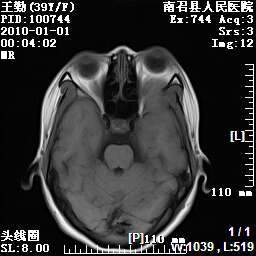

以下是引用随光逐影在2010-1-22 9:03:00的发言:[br]考虑左侧中颅窝(蝶骨翼区)脑膜瘤侵犯蝶骨翼并突入左侧眼眶。

以下是引用水过无痕在2010-1-22 14:55:00的发言:[br]一、定位:颅外占位;二、定性:恶性可能性大;三、组织来源:来源于左侧眼外直肌或其他部位;考虑为:横纹肌肉瘤>转移瘤>脑膜瘤.